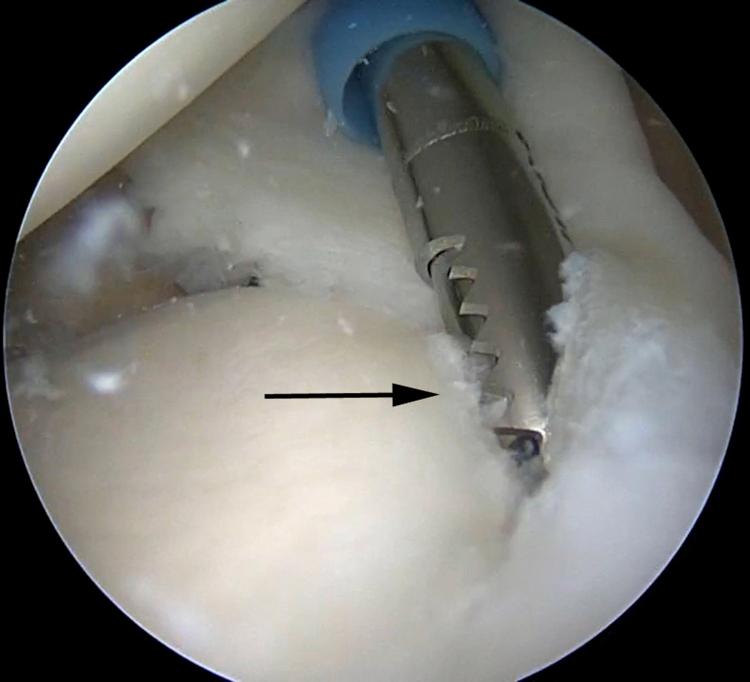

SLAP tears have been a controversial topic in shoulder surgery for decades. The indications for repair of SLAP tears, as well as the methods of repair, have undergone a recent evolution. The use of intra-articular knots for SLAP repair has fallen out of favor because of potential abrasive damage to the rotator cuff and glenohumeral articular cartilage due to knot migration and prominence. In response to this potential iatrogenic injury, arthroscopic techniques have undergone an evolution using advanced techniques with low-profile knotless repairs. We describe our preferred low-profile knotless technique for SLAP repair using LabralTape (Arthrex) in a horizontal mattress configuration.

几十年来,肩袖上盂唇(SLAP)损伤一直是肩部手术中颇具争议的话题。SLAP损伤的修复指征以及修复方法最近都有所发展。由于结的迁移和突出可能对肩袖和肱盂关节软骨造成潜在的磨损损伤,关节内打结用于SLAP修复已不再受青睐。针对这种潜在的医源性损伤,关节镜技术已发展为采用先进技术进行低轮廓无结修复。我们描述了一种使用LabralTape(Arthrex)以水平褥式缝合方式进行SLAP修复的首选低轮廓无结技术。